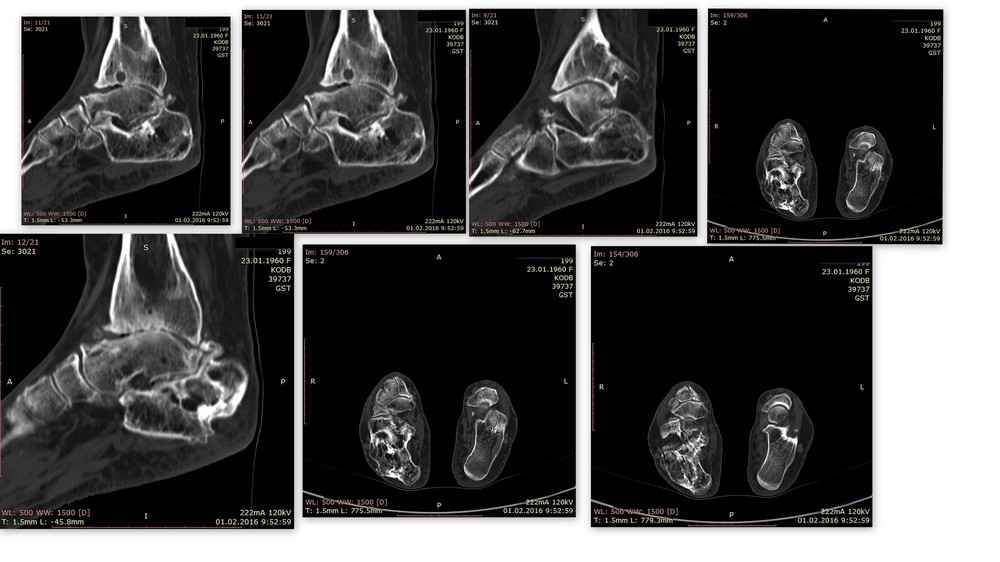

Уважаемые коллеги, прошу Вас выразить свое мнение по поводу тактики лечения. Пациентка 56 лет -наша коллега. Травма в ДТП более 20 лет - открытый оскольчатый перелом костей левого голеностопного сустава,осложнившийся остеомиелитом.

Лечилась скелетным вытяжение, клиника остеомиелита купирована. На данный момент- в последние годы беспокоит стойким болевой симптом в голеностопном суставе, купирующийся анальгетиками на фоне регулярных блокад. Принимает варфарин. Спасибо за помощь.

Мы также больше склоняемся к артродезу, т. к. от суставов практически ничего не осталось, и на наш взгляд, вряд ли купирования болевого синдрома можно будет добиться другим видом вмешательства. Вопрос больше стоит в плане того, чем фиксировать. Гвоздь? будет ли достаточная стабильность в данном случае? Шурупы? Либо всё-таки аппарат? Имеет ли значение проводимая антикоагулянтная терапия?